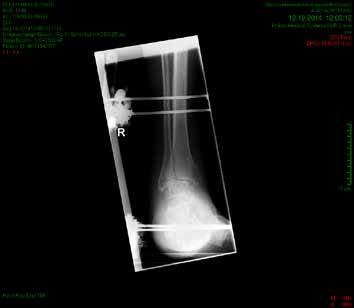

So erhielt ein 67-jähriger männlicher Patient nach operativer Versorgung mittels Fixateur externe neben einer Entlastung nur eine di_CAP-Therapie. Als Hauptdiagnose wurde eine sekundäre Fußfehlstellung in Pes-cavovarus-Position mit chronischem Ulcus am rechten Fußrand bei diabetischer Neuroosteoarthropathie festgehalten (Abb. 2); relevante Nebendiagnosen waren eine pAVK und diabetische Nephropathie. Als operative Therapie wurde eine Stellungskorrektur mit dem Hoffmannschen Fixateur externe durchgeführt (Abb. 3). Intraoperativ konnte eine bakterielle Besiedlung mit Escherichia coli, Enterococcus faecalis und Enterobacter cloacae nachgewiesen werden. Während des stationären Aufenthaltes wurde der Patient zweimal wöchentlich mit di_CAP behandelt. Nach seiner Entlassung erfolgte die Einbestellung zur di_CAP-Therapie nach der 4., 6. und 10. postoperativen Woche. Dabei wurde vor jeder Wundbehandlung ein Abstrich für eine mikrobiologische Untersuchung genommen. Im Verlauf kam es zu einer guten Wundheilung des anfänglich 3 × 5 cm messenden plantaren Ulcus, und in der 10. postoperativen Woche ließ sich eine fast vollkommene Wundheilung beobachten (Abb. 4). Ab der 1. postoperativen Woche war in den mikrobiologischen Abstrichen nur noch E. faecalis nachweisbar, und ab der 4. Woche konnte im Ulcus kein Keim mehr nachgewiesen werden. Aufgrund der geringen Patientenanzahl und der unregelmäßigen Wiedervorstellungen der Patienten konnte die Kohorte nicht suffizient im Verlauf beobachtet werden, um genügend Daten für eine prospektive Studie zu generieren. Die klinischen Erfahrungen der Verfasser decken sich jedoch mit Ergebnissen bisheriger Arbeiten zur di_CAP-Therapie.